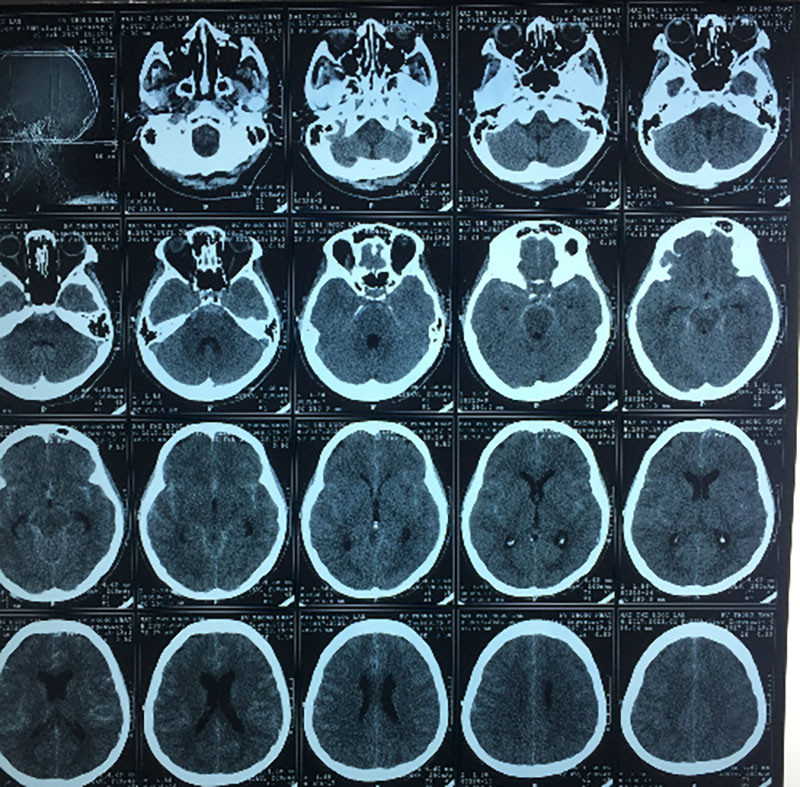

Sau khi chụp CT đầu, Trân Trân bị chẩn đoán xuất huyết não cấp tính ở hạch nền trái của não, lượng máu chảy ra đã là 20 ml. May mắn cô đã được đưa đi cấp cứu kịp thời nên xuất huyết não vẫn chưa xâm lấn tâm thất.